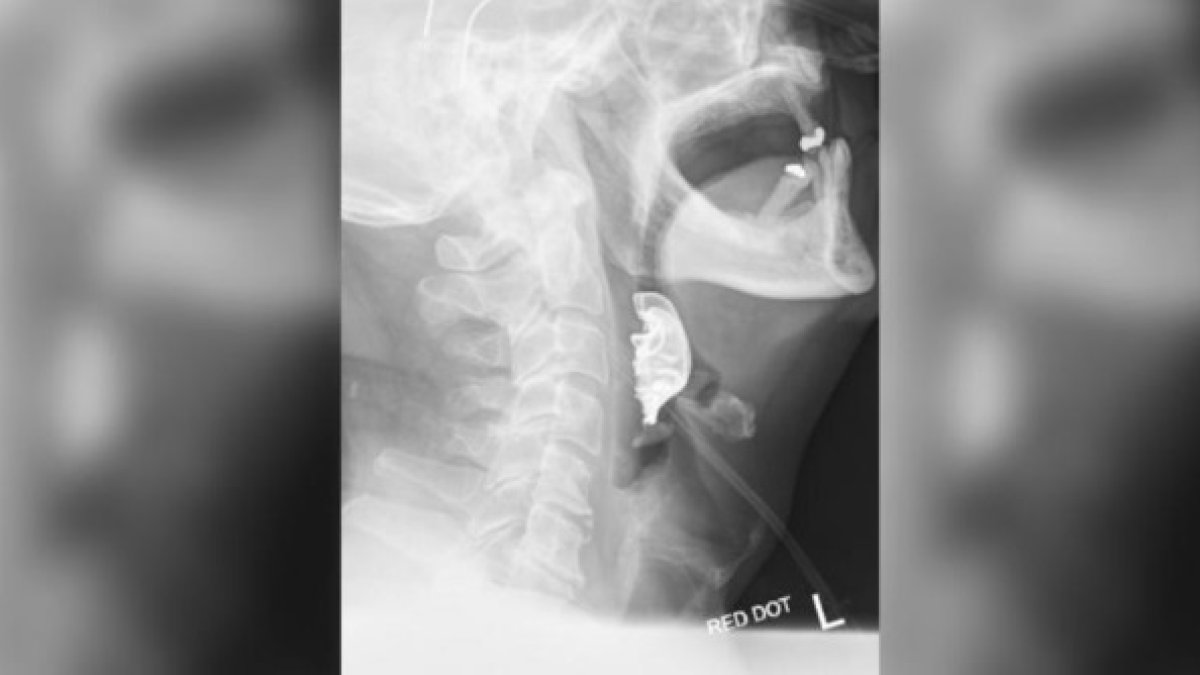

A través del examen de Rayos X los médicos lograron encontrar la dentadura del hombre.

Finalmente, en el análisis de rayos x realizado a su garganta, lograron encontrar al verdadero causante de las molestias del hombre. Su dentadura postiza estuvo todo el tiempo atorada en su garganta, pese a las continuas advertencias que él les hizo a los profesionales sobre las molestias y la perdida de su dentadura.